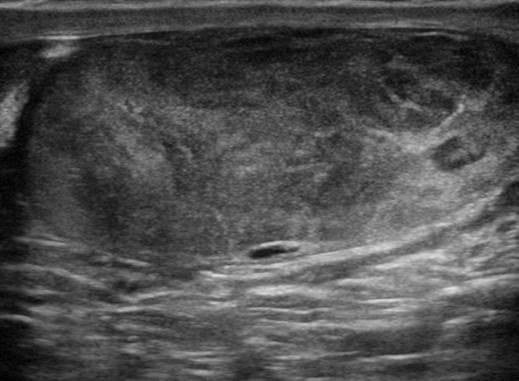

U tinh hoàn

» Thông tin: Nam giới – 35 tuổi.

» Lâm sàng: Sưng tinh hoàn.

# U tinh bào (Seminoma).